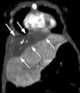

Cystic teratoma of diaphragm